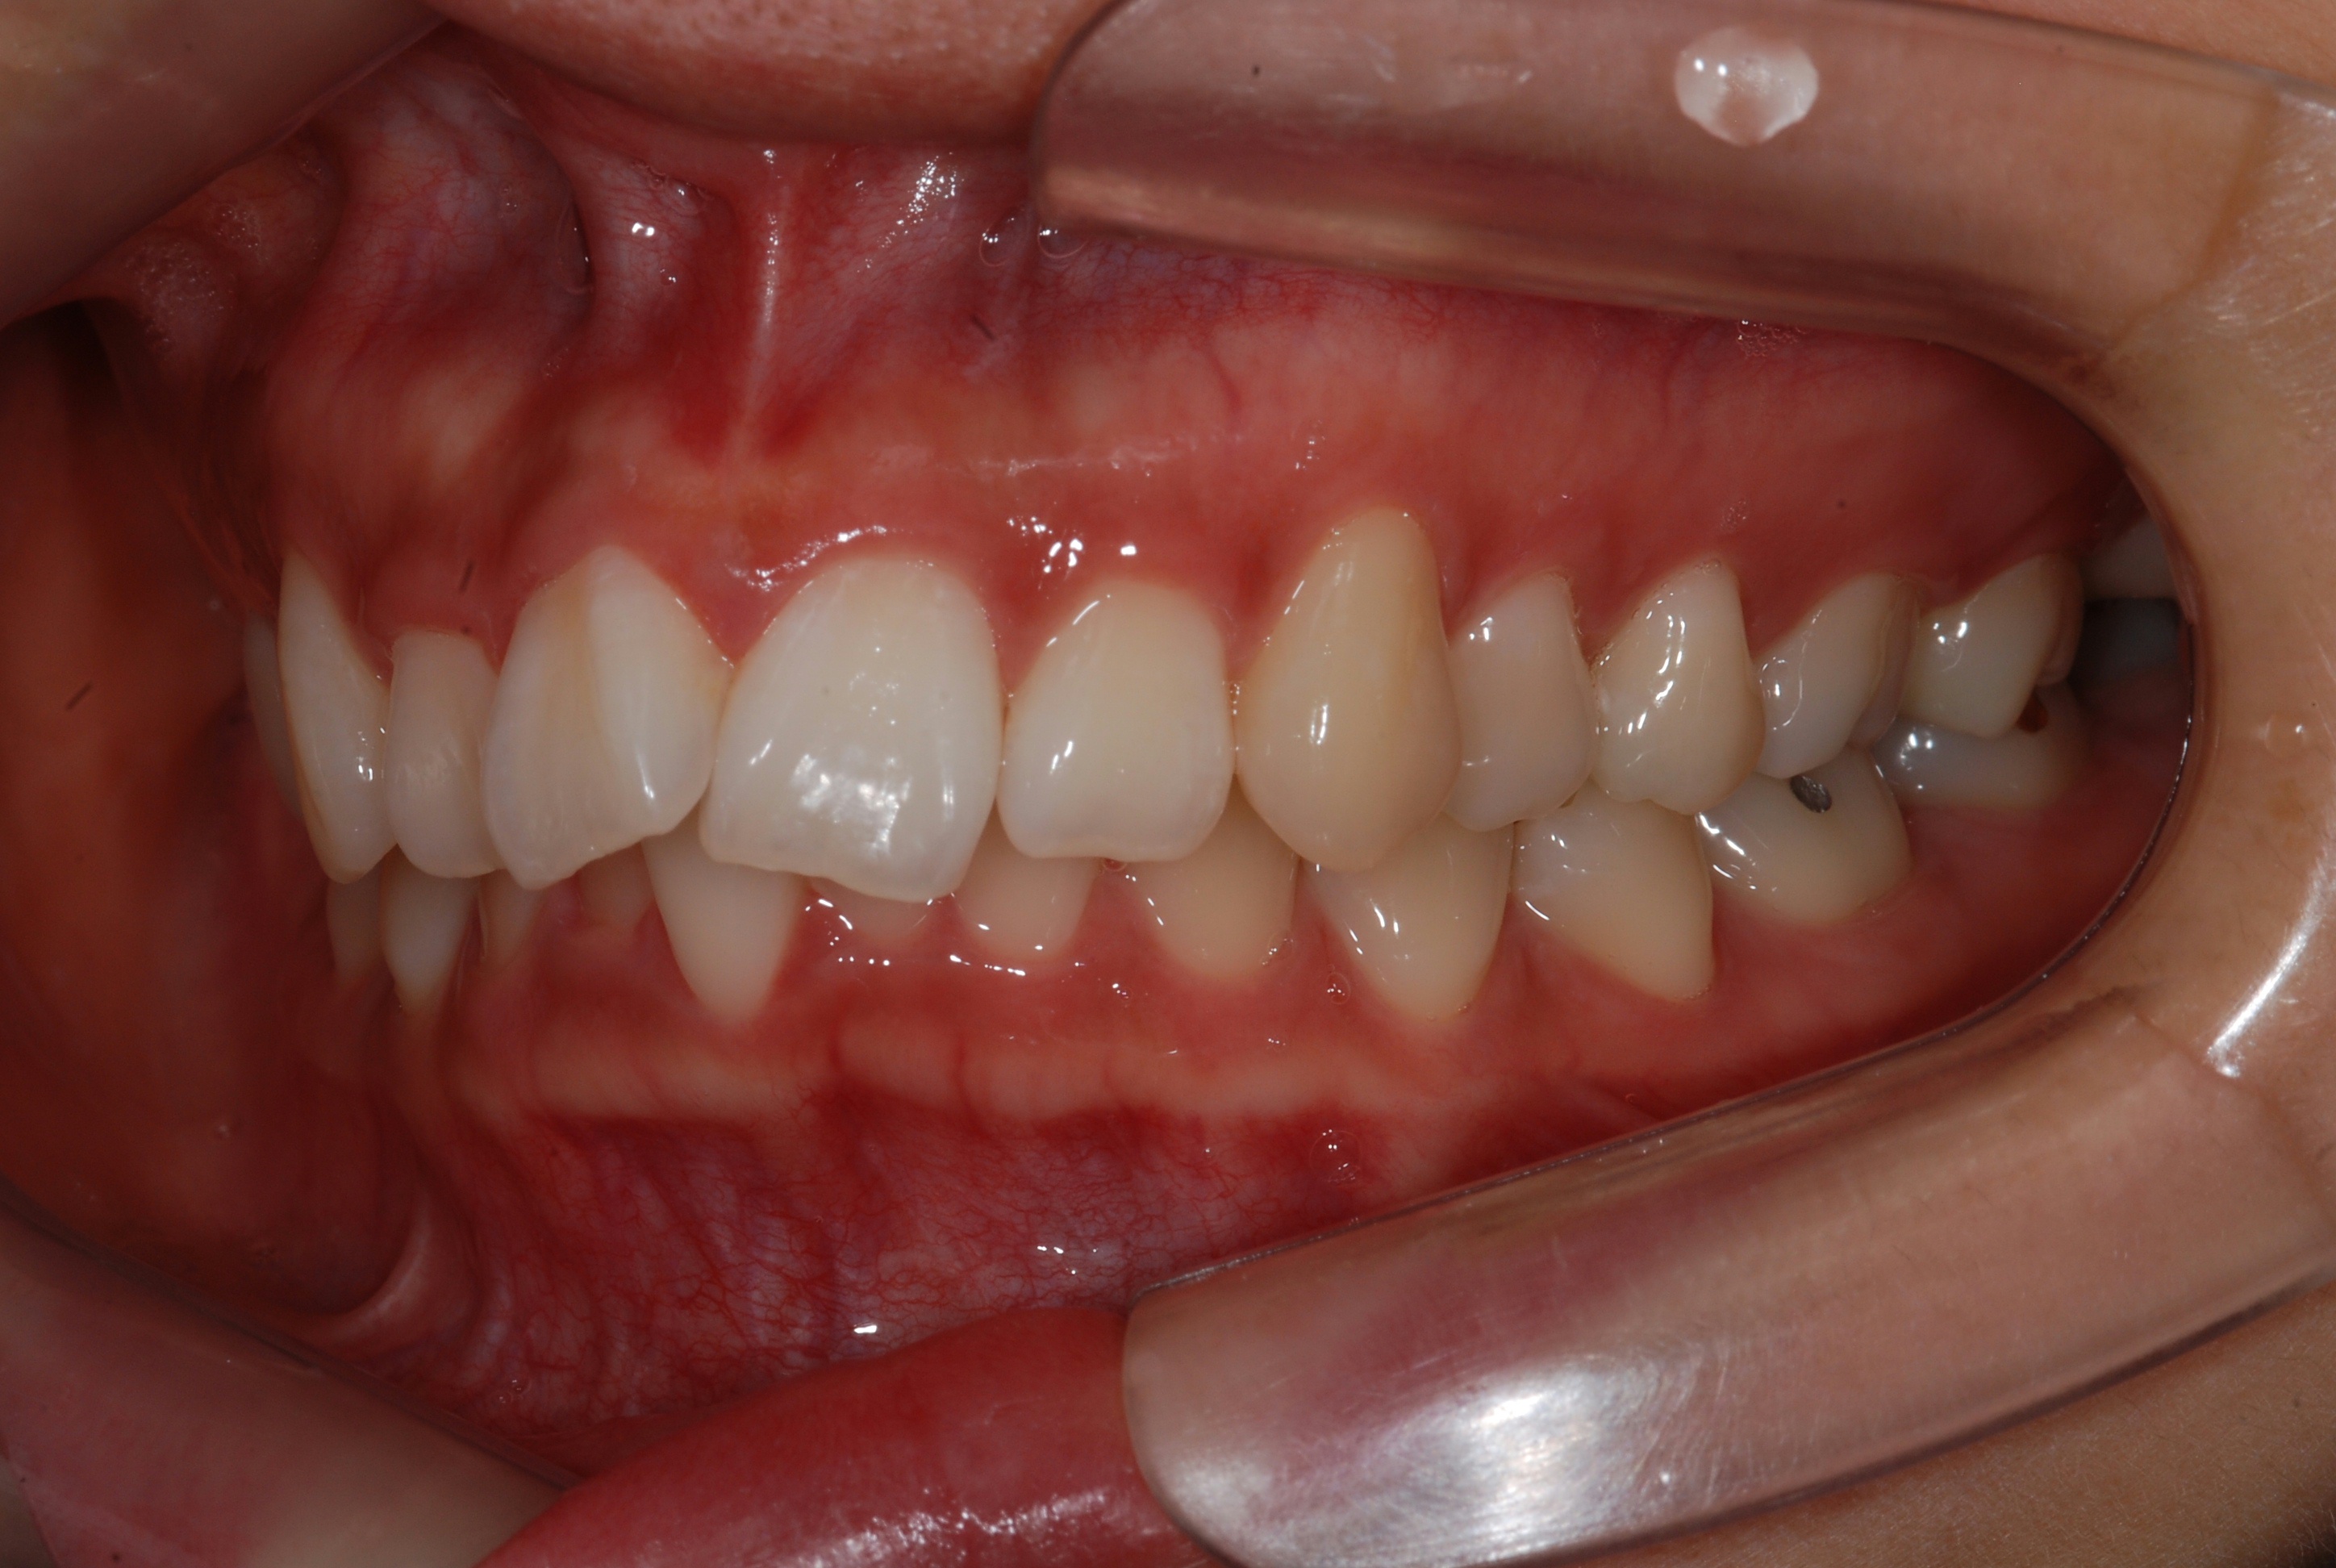

치료 전 사진입니다.